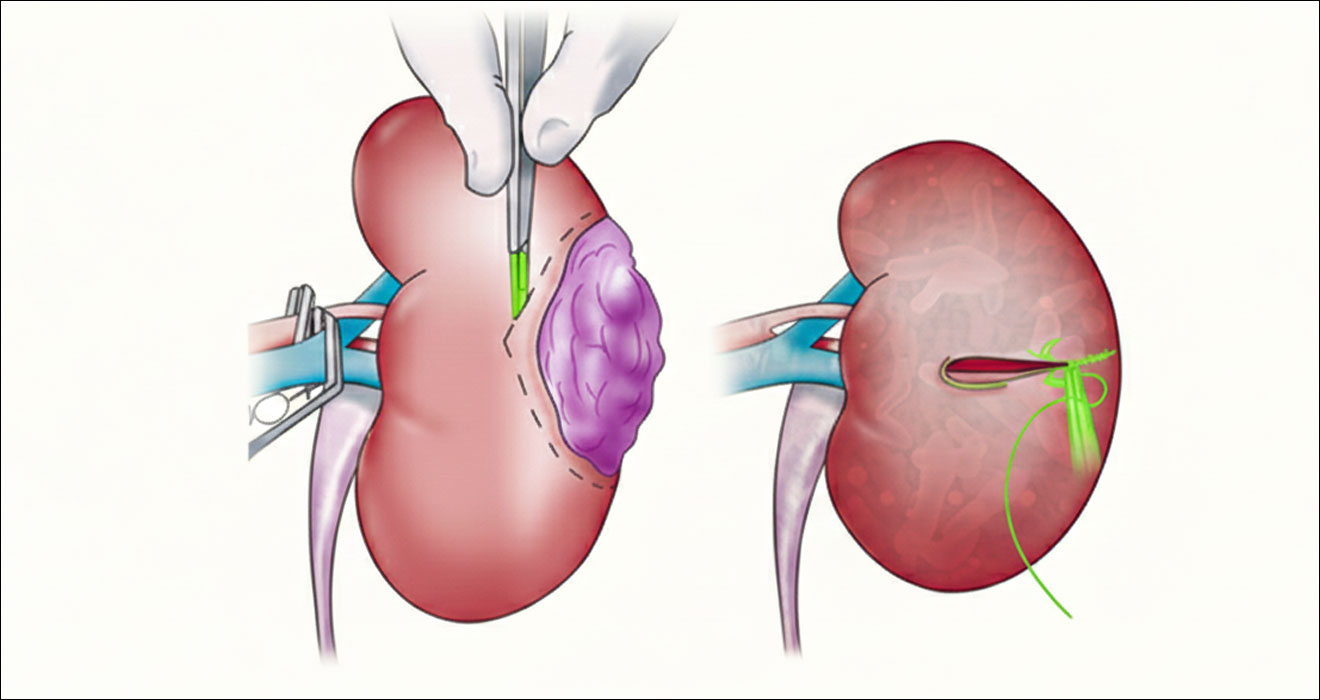

Kidney Cancer Treatment

Treatment for kidney cancer (Renal Cell Carcinoma or RCC) is almost always surgical.

- Partial Nephrectomy (Kidney Sparing Surgery):For smaller tumors, only the tumor and a rim of healthy tissue are removed, preserving the rest of the kidney’s function. We specialize in robotic partial nephrectomy, which allows for a highly precise and quick removal of the tumor, crucial for those who have restricted renal functions.